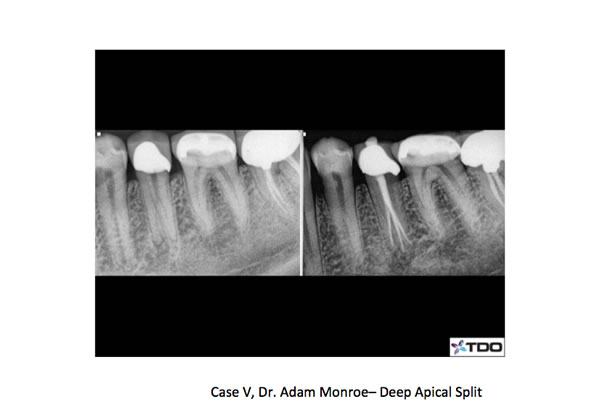

We recommend an ovoid access starting under the buccal cusp tip and extending lingual. The mandibular bicsupids can present with a lingual incline which needs to be taken into consideration when accessing under high magnification. When two canals are present, they almost always present as a buccal and lingual canal. When a deep split occurs the split usually takes place in the apical third or last several millimeters of the root. Three canals have also been reported especially in certain population subsets around the world. The mandibular first bicuspid presents with two canals more often than the second bicuspid. A well know study by Frank Vertucci in the late seventies reported the presence of two canals at the root apex nearly 25 % of the time and three canals in .5% of mandibular first bicuspids!

Preoperative awareness of additional anatomy can certainly increase detection and successful treatment of multiple canals. Examining off angle radiographs for the presence of an extra PDL can indicate multiple roots or canals. Clinically, the anatomy of the cervical area of the tooth can also hint of extra or atypical anatomy. In treating these teeth it is important to use small hand files first to explore the canal walls. A catch or deflection of the file in one direction should lead to increased suspicion of additional anatomy. Once the canals are located a thin, fine diamond can be used to flare the axial walls to ensure straight line access to each canal. I also like the use of MUNCE burs for access deep into the canal system, especially under high magnification with the micoscope. One additional complication in treating these teeth is the difficulty with obturation. Many times fitting multiple cones can be tough and can lead to “crinkling” of the cone tip. In the case of a deep split, it may be helpful to use an endodontic plugger to keep one canal patent while filling (or backfilling) an adjacent canal. I have included several cases below that were recently treated in our office. Many of these cases require more time than one would usually expect for a mandibular bicuspid. A pre-operative awareness of the manidbular bicuspid anatomy, careful instrumentation and allotting extra time will help lead to successful treatment of these cases.